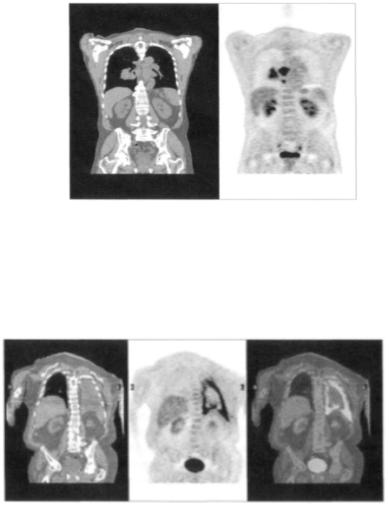

Рис. 10. Корональное изображение пациента с мелко-клеточным раком лёгкого. Показано повреждение, представленное большим накоплением ФДГ в правом корне и средостении. Определяется нормальное накопление активности в печени, селезёнке, почках, уретре и мочевом пузыре.

Рис. 11. Корональные КТ (А) и ПЭТ (В) у пациента с лихорадкой и выраженной болью с левой стороны в грудной клетке с известным в анамнезе ингаляцией асбеста и диагностированной

мезотелиомой. Совмещённое ПЭТ/КТ изображение показывает точную локализацию интенсивности наопления ФДГ на анатомическом КТ скане.